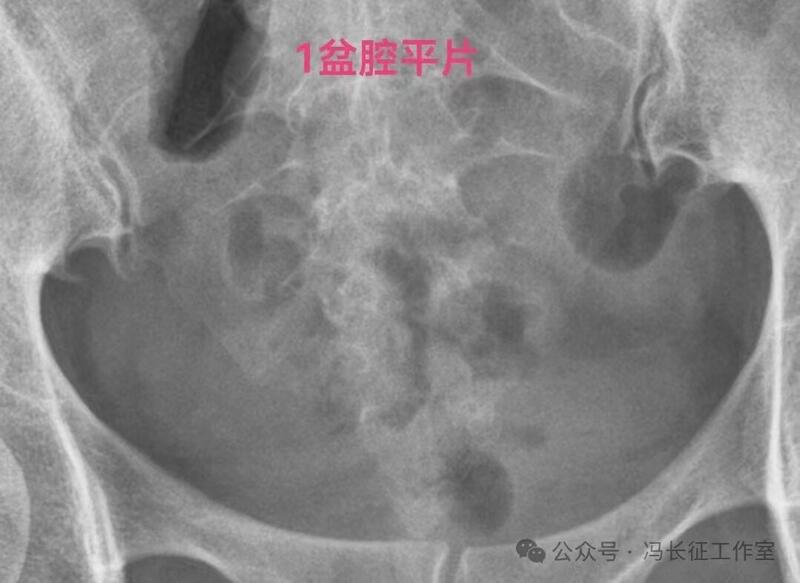

下面是一例输卵管功能良好的双侧输卵管积水的图片

双侧输卵管输卵管走行较自然柔软,近端和宫腔相通,输卵管粘膜丰富、单囊,双侧输卵管都向中间的子宫聚拢(提示输卵管系膜好),这些都提示双侧输卵管功能良好。虽然伞端没有造影剂进入盆腔弥散,输卵管管壁厚度和周围粘连情况未知;但是,从前面的信息可以初步估计输卵管功能良好。所以就给她做了腹腔镜行积水远端造口手,恢复伞部的拾卵功能,术后自然怀孕生育。